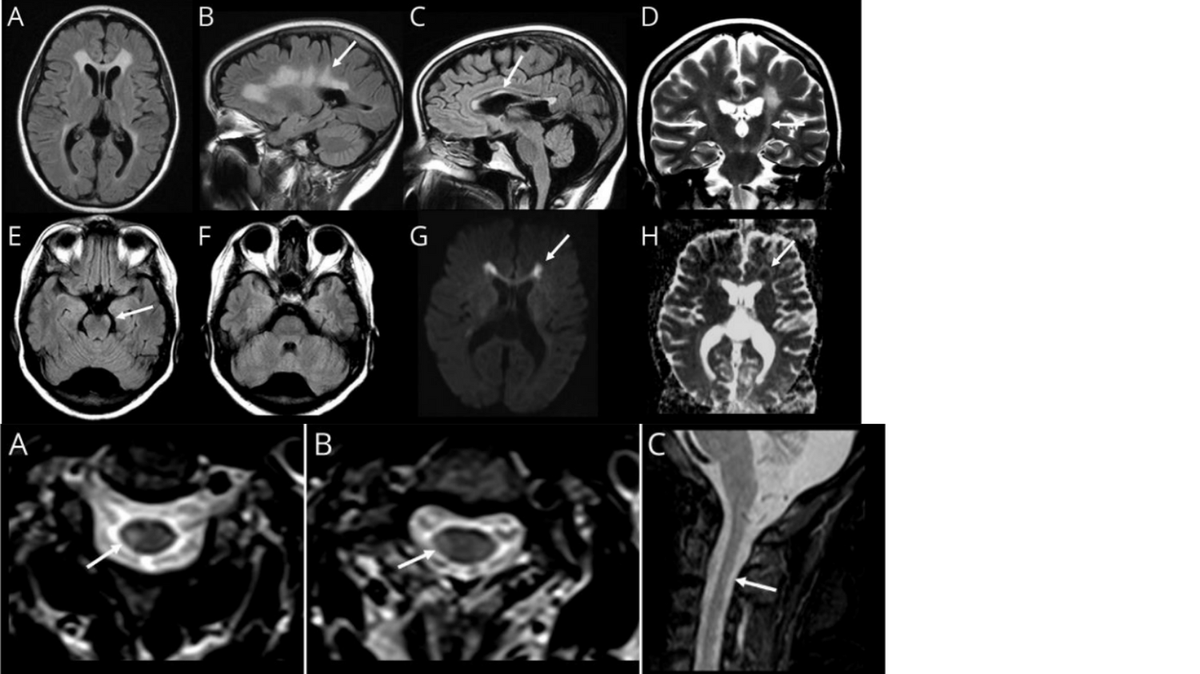

46 year old woman with progressive cognitive impairment and parkinsonism diagnosed with MS and given mayzent. What is the real diagnosis? Hint: The finding on panel G was persistent on multiple MRI scans. Hint #2: This condition rarely involves the spine.

Dr. Brandon Beaber tweet media